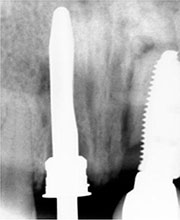

Poste direccional del implante

Radiografía del poste de guía